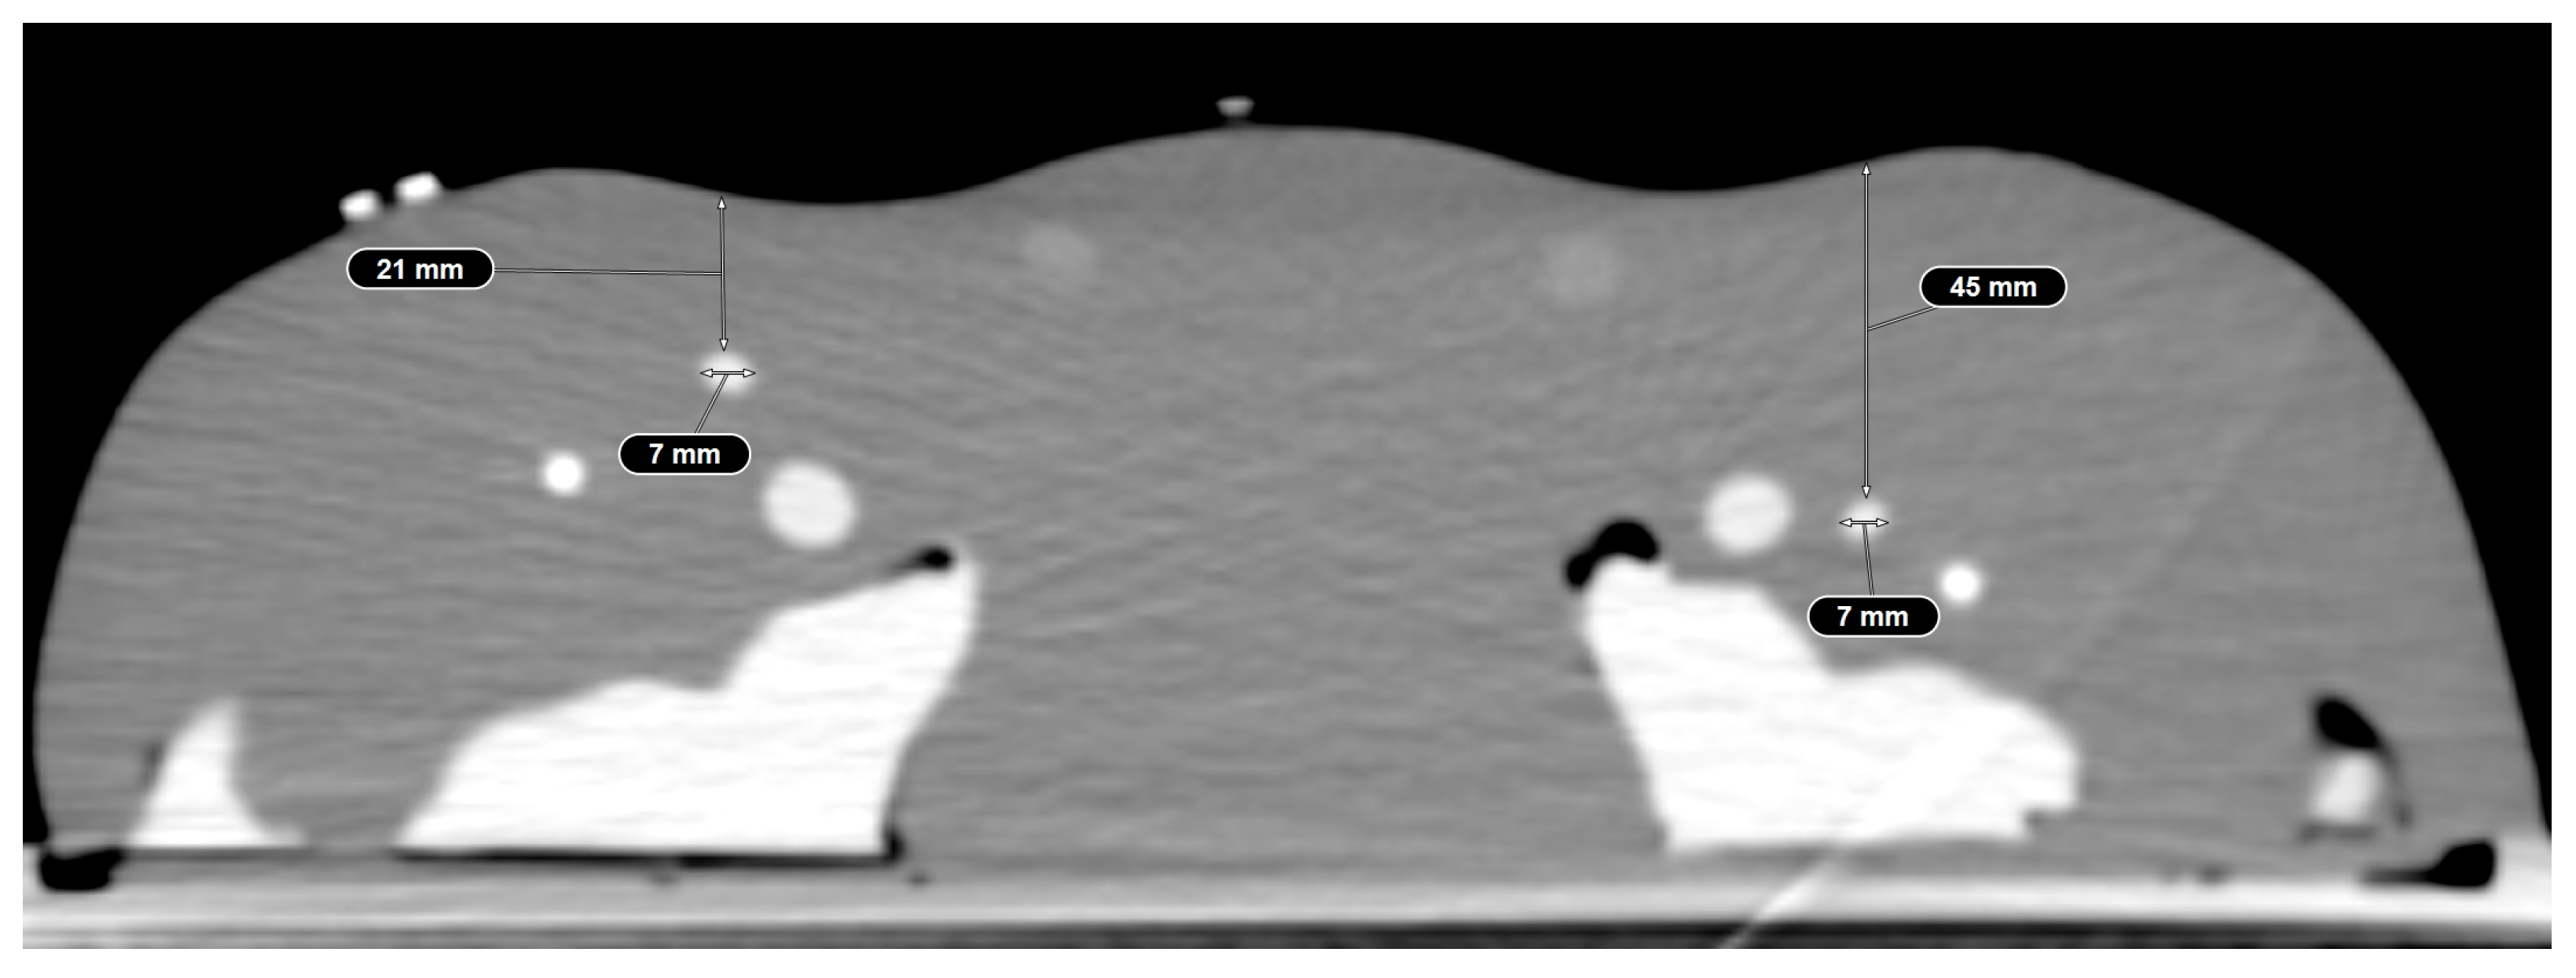

2.1. Phantom Model